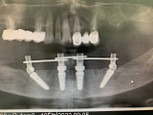

Кабинет стоматолога Самедова Нусрета Исабалаевича специализируется на диагностике и лечении заболеваний зубов и десен.

В клинику можно обратиться как для проведения профилактических процедур, таких как отбеливание и чистка зубов, так и для исправления прикуса брекет-системами и элайнерами, удаления, протезирования и имплантации зубов и зубного ряда.